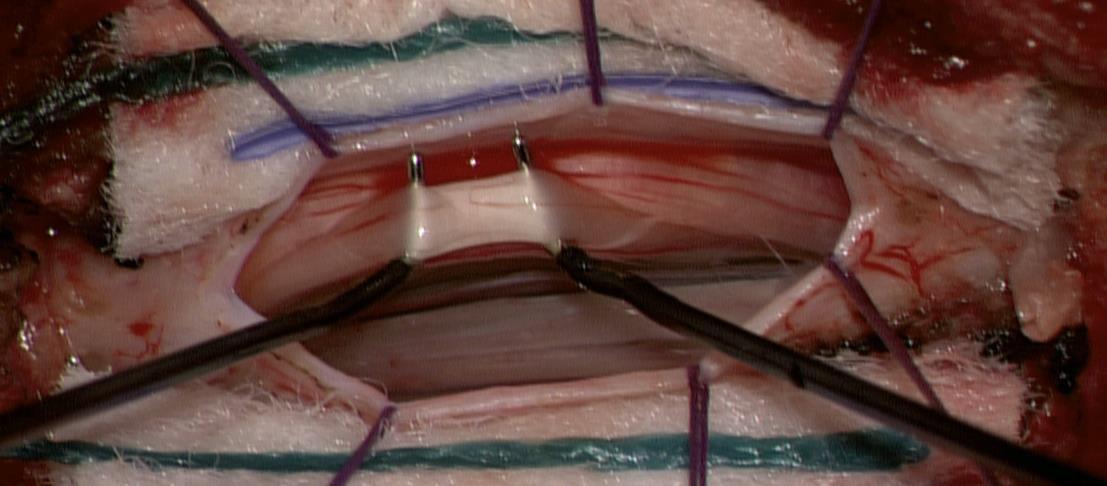

Transcranial Motor Evoked potentials (TcMEPs)

Somatosensory Evoked potentials (SEPs)

Bulbo-cavernosus reflex (SEPs)

SDR involves surgically accessing the spinal cord (typically in the lumbosacral region, L2 to S1 or S2).The dorsal (sensory) nerve roots are carefully identified and then divided into smaller bundles called rootlets.

0 Unsustained or single discharge to train of stimuli

1+ Sustained discharge of appropriate muscle group. Ipsilateral response

2+ Sustained discharges of adjacent muscle groups, Ipsilateral

3+ Sustained discharges of distant muscle groups, Ipsilateral

4+ Sustained discharges of contralateral muscle group(s), with or without ipsilateral muscle group involvment